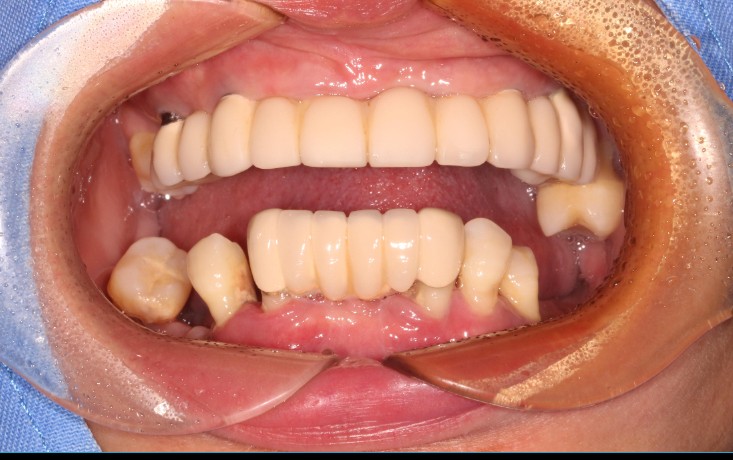

术前图片